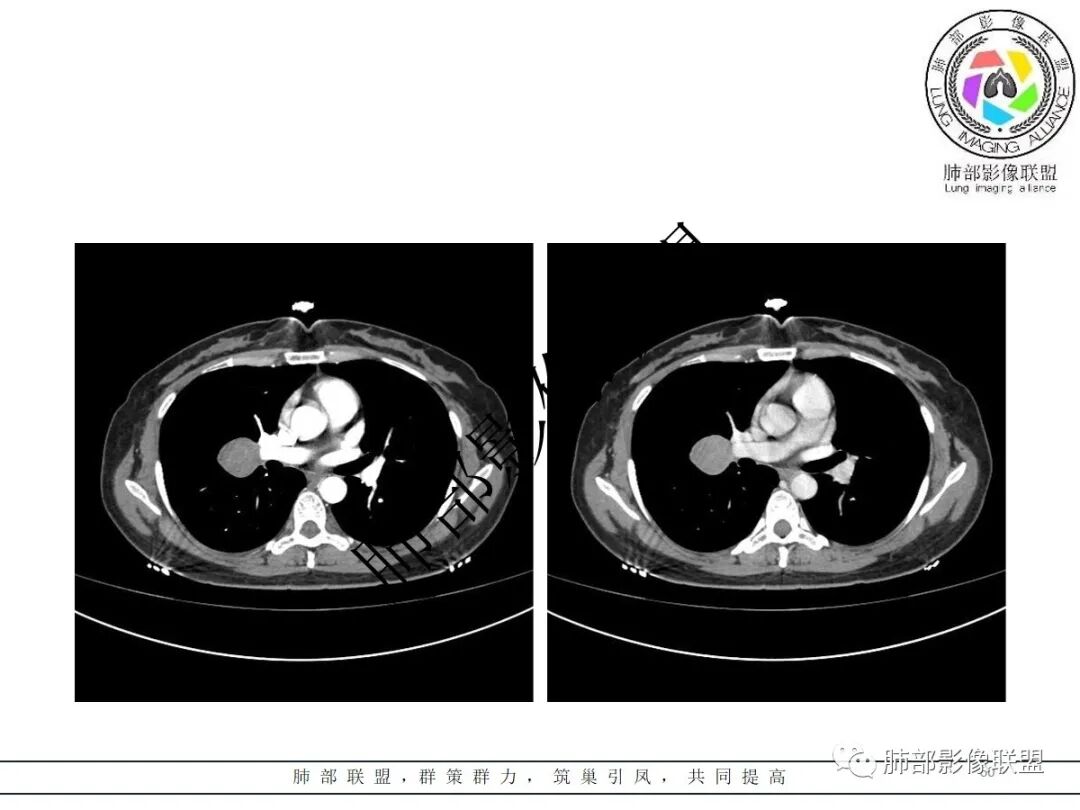

3.病灶密度均匀,未见液化坏死、钙化及脂肪低密度。轻度强化,可见纤细血管影蜿蜒穿行。右肺动脉推移变形,未见侵入或充盈缺损。

4.灶周未见磨玻璃晕或极低密度影环绕。右肺下叶背段胸膜下见微小实性密度结节影,边界清楚。

5.双肺门及纵隔未见增大淋巴结。双侧胸腔未见积液。

3)CT増强多呈中度至明显均匀强化,多期扫描呈持续性强化,部分病灶早期强化不均匀,呈花斑状,延迟后强化较早期均匀;

4)瘤周可出现晕征、空气新月征及贴边血管征,若同时出现,诊断PSP的信心更好。